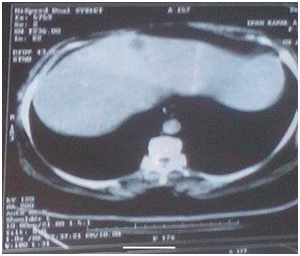

Thirty-three patients of MTNBC presented in a period from February 2013 to March 2015 were treated with gemcitabine\carboplatin. Patients had a median age of 43.6years (range, 24-71 years, S.D: 11.161)23 patients were premenopausal (69.7%) & 10 patients were postmenopausal (30.3%). Approximately 81% of patients had a good PS (0-1). 12 patients were basal subtype (positive ck5/6) from twenty patients who had accessible specimens for examination of cytokeratin (12out of 20=60%), Mean overall survival (OS) in patients has basal subtype were 12 months, while in patients has non-basal subtype were 12.96 months (95% CI-3.53-5.45) P <0.242). Median progression-free survival (PFS) in basal subtype were 5.857 months while in non-basal subtype were 6.15 months (95% CI-1.79738-2.39079) P <0.456).patient had complete response (CR) Figure 1.

Figure 1 Liver metastasis, a. Before treatment & b. After treatment.